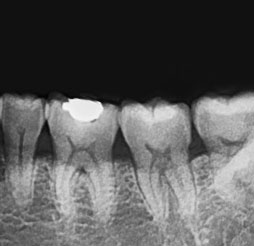

[ 拍摄牙根 ]

* 需要时拍摄为了更仔细, 精密的检查问题牙齿拍摄X光片,

牙根底部炎症, 牙齿根管状态, 一般蛀牙等2次蛀牙都能确认 .